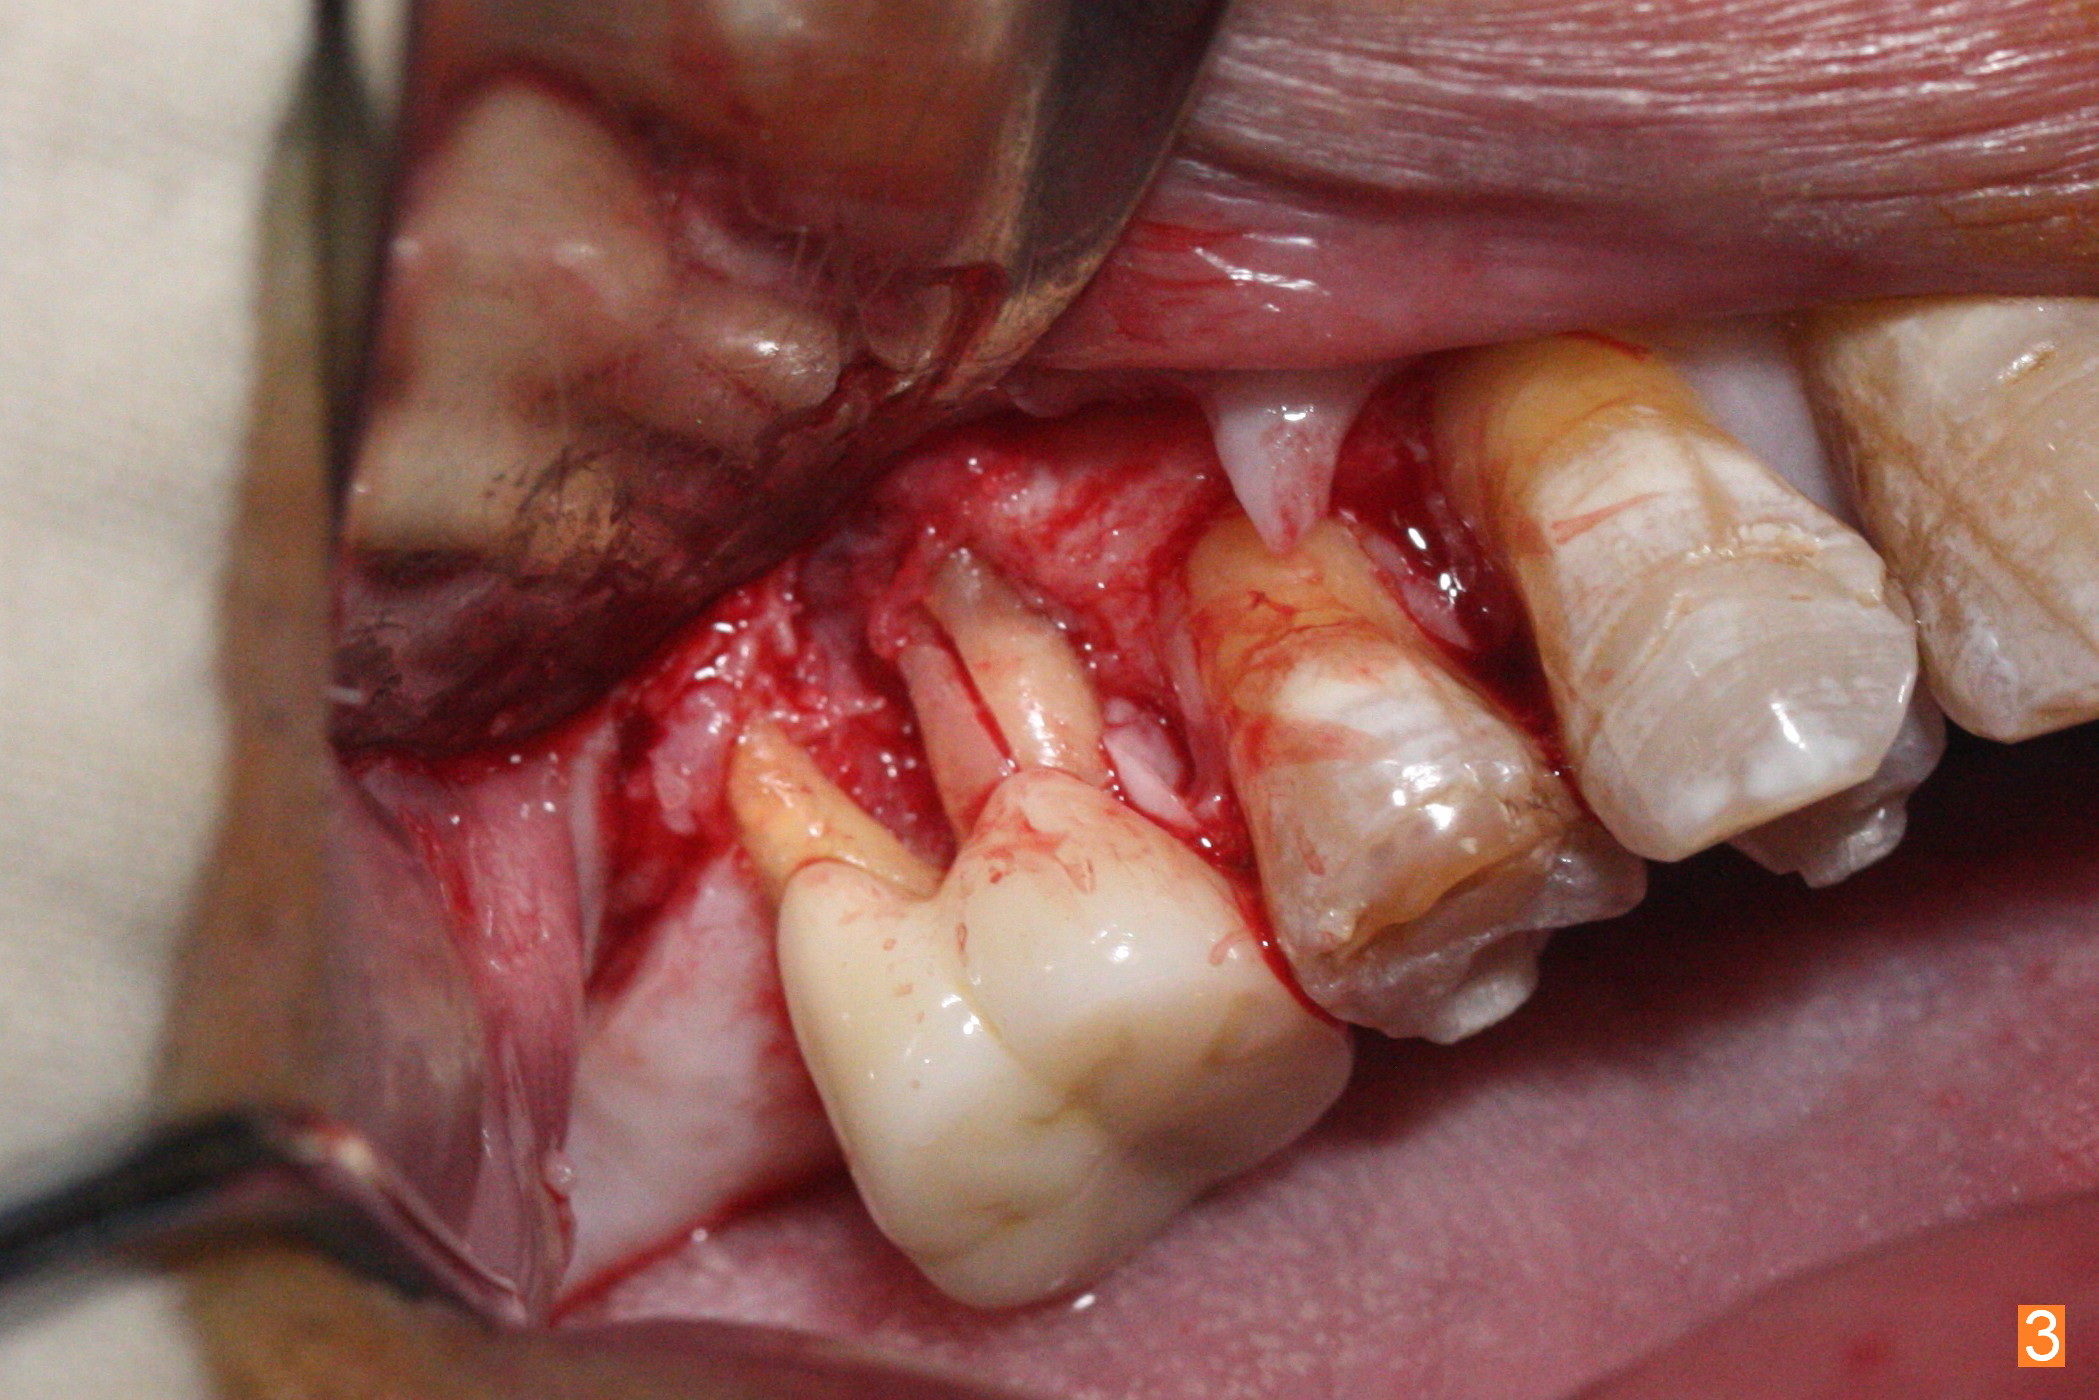

A 56-year-old man has discomfort associated with the tooth #3 one year and a half after root canal therapy (Fig.1: mesiobuccal root vertical fracture). Since an implant is just placed at #19 and another one will be encouraged to be placed at #2 (Fig.2), root amputation may be a valid treatment modality (Fig.3,4). After debridement and Clindamycin topical application, allograft/Osteogen is placed (Fig.5,6 (dashed line)), followed by Osteogen plug (Fig.7 *). Discomfort apparently shifts to the distobuccal root 9 months postop, while the MB defect seems to heal (Fig.8 *). Extraction and implant is expected.